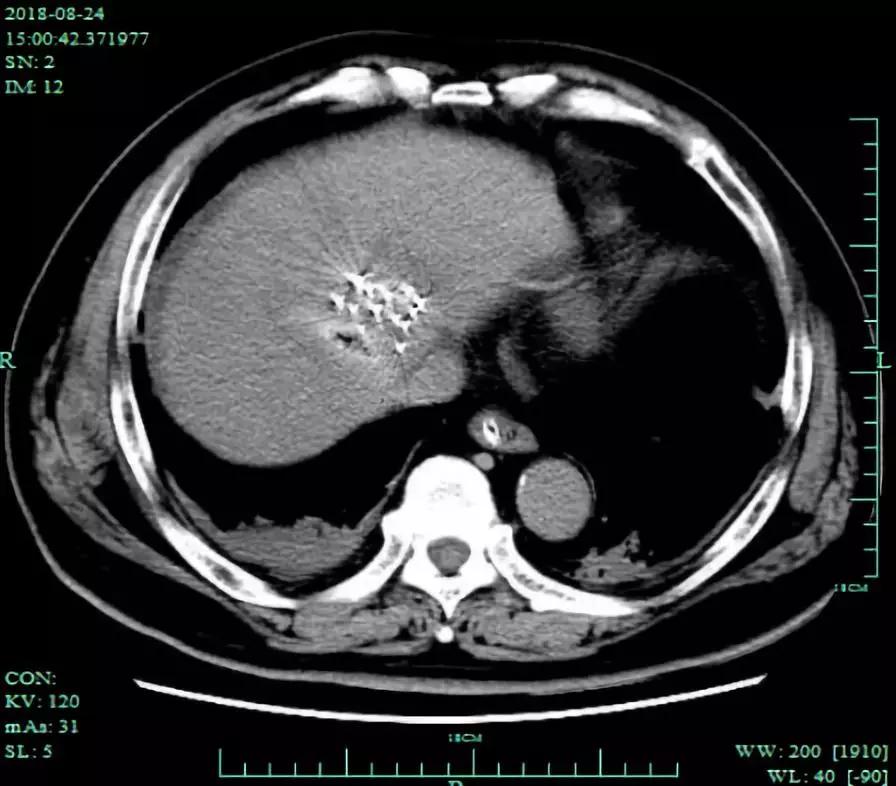

术后CT和MRI复查,显示粒子植入位置良好,消融病灶完全灭活。

术后CT平扫可见粒子植入位置良好